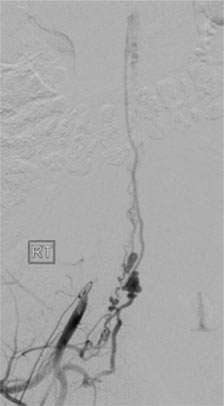

Figure 4: Catheter Embolization of a Spinal Dural AVF.

A microcatheter was navigated into a spinal dural AVF.

From the microcatheter, glue was injected into the AVF. After this, the lesion disappeared completely.